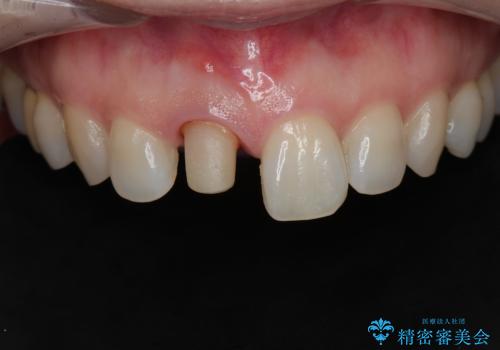

- 前歯が気になるとの事で来院。保険の被せ物(プラスチック素材)メタルの土台が入っていたので

拡大鏡下で全て除去し精密根管治療を行いセラミックの被せ物を装着しました。